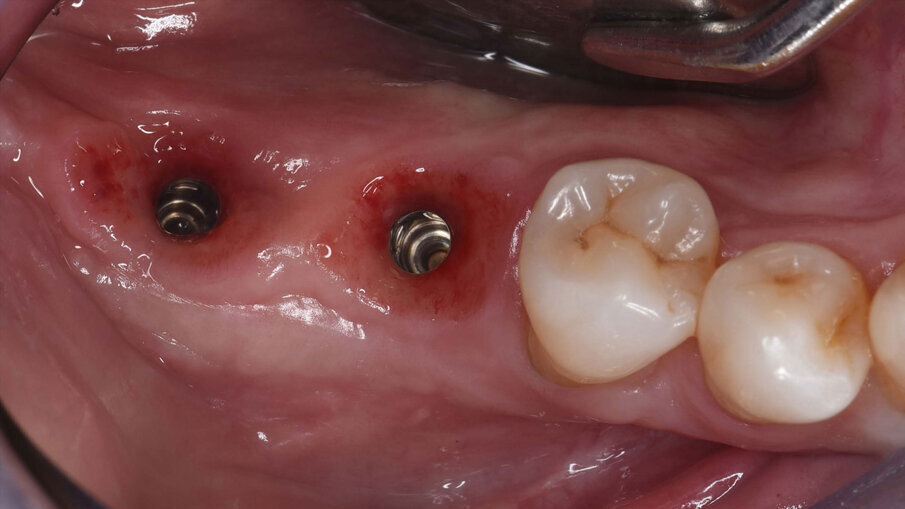

Figg. 1a-1c_Foto clinica e sezioni di CBCT iniziali in cui si evidenzia edentulia distale all’elemento 4.5 con atrofia tridimensionale.

Fig. 10_Foto clinica che mostra la scopertura dei due impianti nel tessuto rigenerato, eseguita nella seduta di rimozione della griglia.